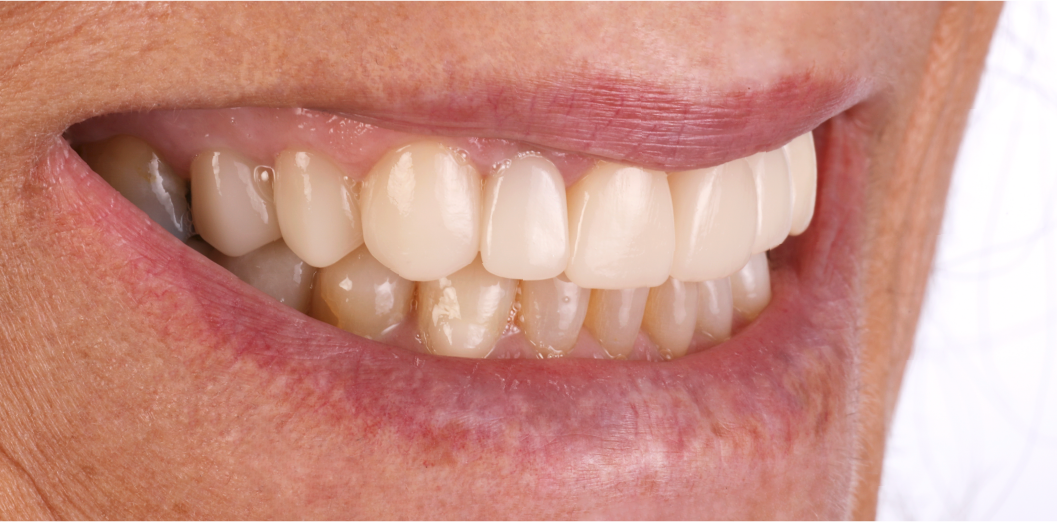

Antes e Depois do sorriso da paciente.